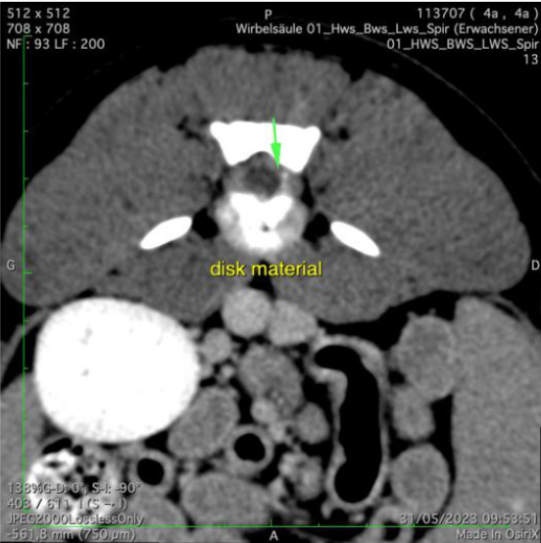

Der Patient wird neurologisch untersucht. Er ist hinten kraftlos und zeigt eine stark reduzierte Schmerzempfindlichkeit sowie einen Koordinationsverlust beider Hinterbeine. Die Kniescheibenreflexe sind gesteigert. Zusammengefasst weisen die Befunde auf eine Störung im Bereich des Lenden-Rückenmarkes hin; aufgrund des akuten Auftretens und der Rasse des Hundes steht die Verdachtsdiagnose eines Bandscheibenvorfalls im Vordergrund. Der Hund wird notfallmässig an ein Spital überwiesen, wo ein Computer-Tomogramm der Wirbelsäule angefertigt wird. Hier wird ersichtlich, dass das Tier tatsächlich an einem akuten Bandscheibenvorfall leidet: Teile der Bandscheibe zwischen dem 4. und 5. Lendenwirbel sind in den Rückenmarkskanal gequetscht worden und drücken auf die empfindlichen Nervenbahnen (grüne Pfeile). Der Rüde wird operiert, das Bandscheibenmaterial wird mittels einer sogenannten Hemilaminektomie entfernt.